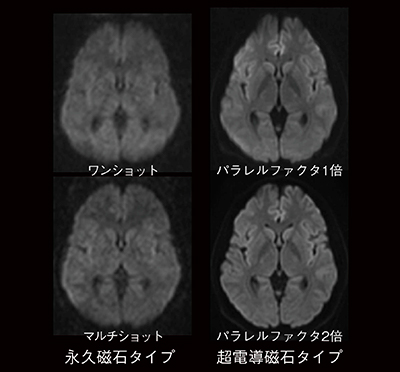

6.DWI撮像(図6)

EPI法によるDWIの撮像では歪みが問題となり,位相方向の選択が重要となります。また,この歪みの抑制にはパラレルイメージングが有効です。永久磁石タイプは歪みの影響が少なく,マルチショット撮像により,歪みを抑えています。

図6 DWI画像の違い